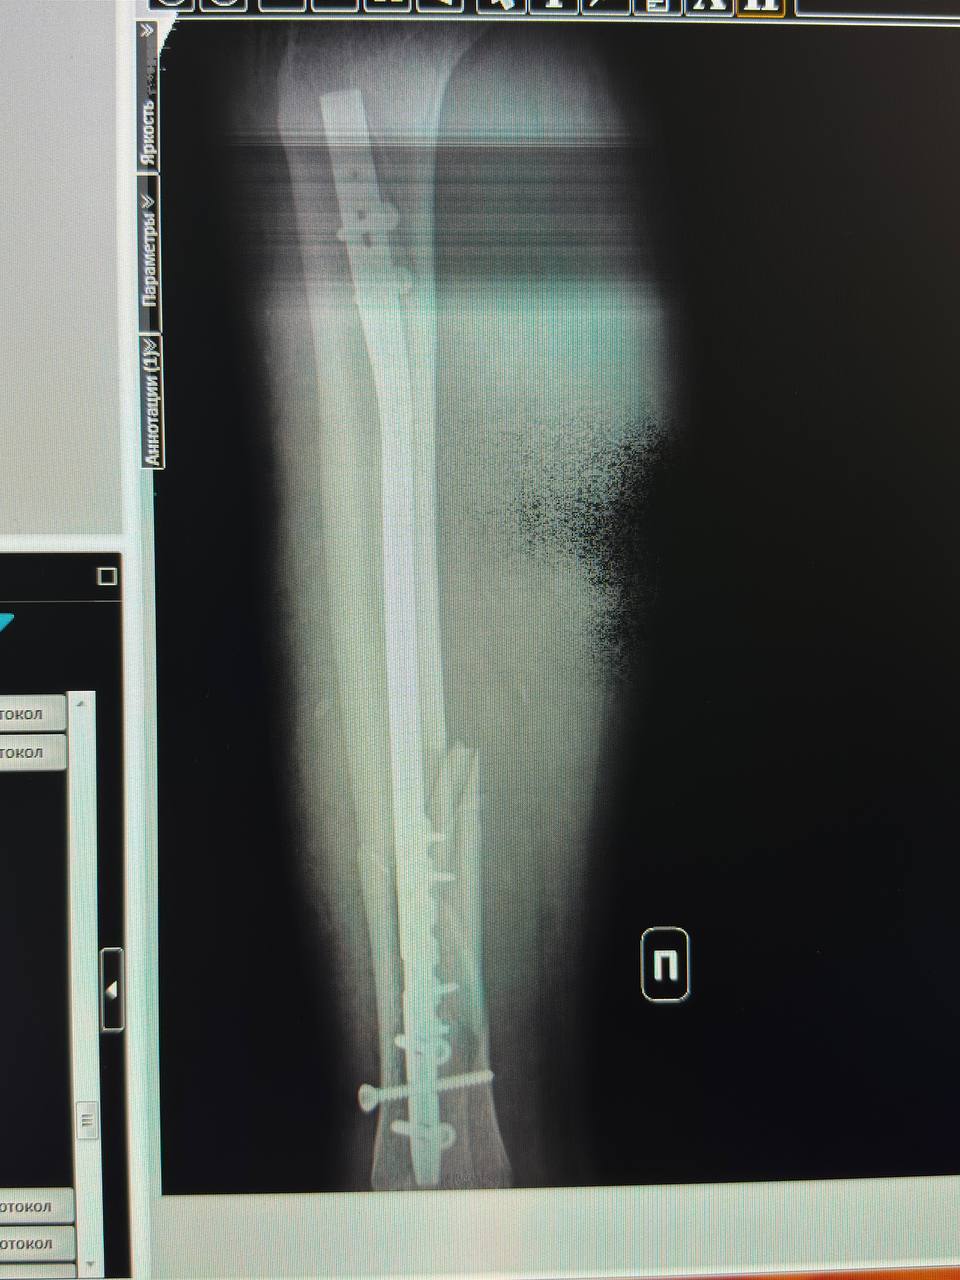

Сломала ногу. Перелом большой и малой берцовой кости. В данный момент лежу в больнице, о чуде на нг можно и не мечтать.... Я мать одиночка с неблагополучной семьи. Так что помощи ждать не откуда. Реабилитация от 3 до месяцев. Соответственно работать не смогу. Прошу помощи как материальной, так и может кто знает куда можно обратиться за помощью. Нужны будут продукты и оплата коммунальных услуг. А также деньги на транспортировку меня.Данные скрыты номер карты моего сына Димы. Буду благодарна любой помощи....PS может кто поможет с работой на удалёнке.